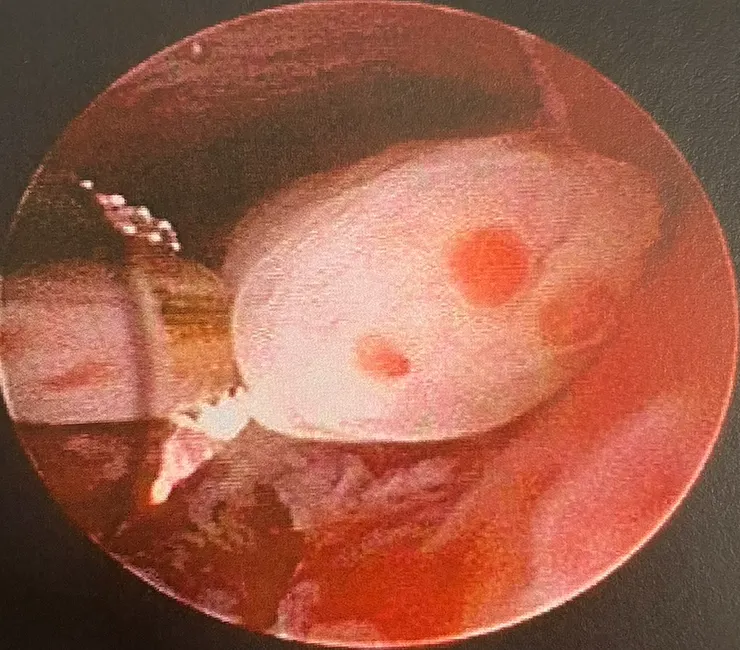

切除了子宮頸一顆,子宮內一顆,然後給我手術中間的照片。照片有速潔刀切除瘜肉的過程,速潔刀的長相被放大很多倍,很像海底生物探勘。我去病歷室申請彩印病歷,想做個紀錄,有需要的話也讓美國Dr.Vu看一下。